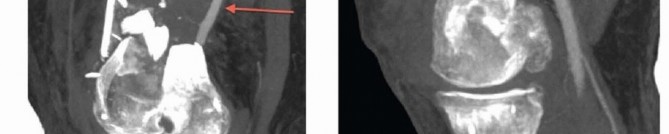

### FIG 17 • A. Patient in FIG 3A after débridement of nonviable extruded bone and placement of external fixator. The segmental bone loss is seen. B,C. Nonunion of a C3 distal femur fracture with subsequent hardware (plate) failure. D,E. Early hardware failure at 3 months (screws) in a C1 distal femur fracture. It has been suggested that the use of a longer plate (longer than nine holes in length with eight holes proximal to the fracture) can minimize failures of fixation. 14 Neurovascular injuries Can occur from initial trauma Rare after surgery Infection 0% to 10% rate after ORIF Predisposing factors High-energy injuries Open fractures Extensive dissection Prolonged operative time Inadequate fixation Nonunion 0% to 19% rate after ORIF Predisposing factors Bone loss or defect ( FIG 17A) High-energy injuries Soft tissue stripping Loss of osseous vascularity Inadequate stabilization No bone graft Infection Malunion More common with nonsurgical treatment, which results in varus and recurvatum Operative treatment with newer locking plates can result in valgus. Malrotation has been reported as high as 38.5%. 2 Treatment required to restore mechanical axis Supracondylar osteotomy Stable fixation Early range of motion Hardware failure occurs in 0% to 13% of cases ( FIG 17B,C, plate; D,E, screws).14, 17 Predisposing factors Comminution of metaphyseal area Older age Very distal fracture Premature loading or weight bearing Open fractures Smoking Increased BMI Shorter plates (less than nine holes of overall length) Diabetes Nonunion Infection Knee stiffness: Almost all patients exhibit some loss of motion. Protruding hardware (see FIG 10E,F) Articular malreduction 491 Adhesions Intra-articular Ligamentous-capsular contractures Muscle scarring Treatment may consist of any or combination of the following: Manipulation Arthroscopic lysis Formal quadricepsplasty Posttraumatic arthritis occurs in 0% to 30% of cases. Predisposing factors Severe articular comminution Cartilage loss Cartilage impaction or damage Surgical factors Failure of anatomic reduction Malalignment of fracture ##